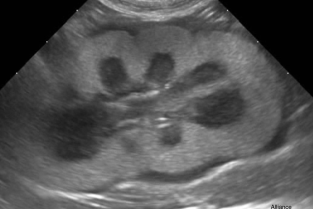

Les consultations pour insuffisance rénale sont nombreuses alors que l’analyse urinaire et les examens biologiques sont bien souvent insuffisants pour en déterminer la cause. L’examen échographique des reins et des uretères est alors un complément indispensable.

Les consultations pour strangurie, dysurie et hématurie sont également un grand classique de nos salles de consultations et un examen échographique de la vessie et de la prostate bien conduit, prend également tout son sens.

Enfin, comment conclure sans examen échographique des surrénales en cas de forte suspicion d’hypercorticisme et après confirmation biologique du dérèglement de l’axe corticotrope ?

- réaliser un examen échographique des reins, de la vessie et de la prostate ;

- connaître et trouver les repères anatomiques pour identifier les glandes surrénales

- reconnaître les affections les plus fréquentes ;